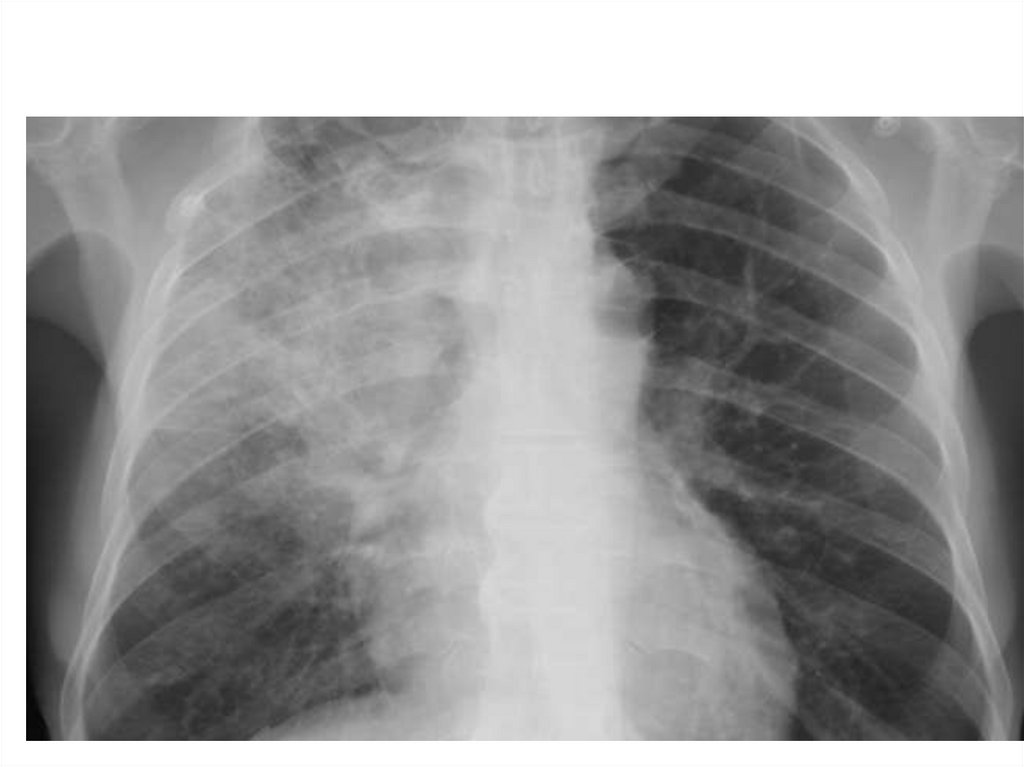

Пневмония